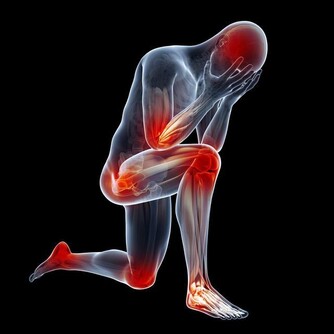

肝癌引起右肩部疼痛就是牽涉痛,

這可能是肝癌壓迫附件的膈肌或肺部以下的肌肉神經所引起的。

而這些被壓著的神經正好是連接右肩的神經,就會引發右肩疼痛。